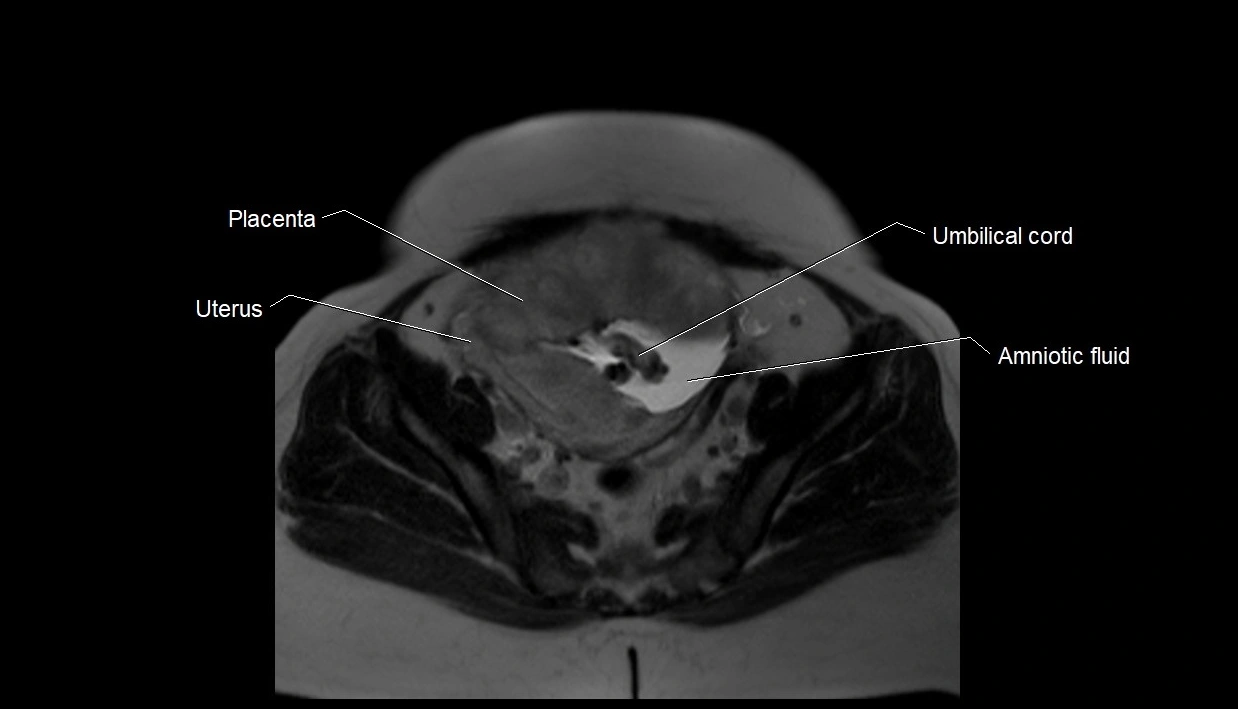

MRI Appearance

T2 HASTE (T2 GRE):

• Amniotic fluid shows very bright hyperintense signal

• Provides natural contrast against fetus and placenta

• Small particles (vernix) may appear as scattered hypointense foci within bright fluid

MRI image

image